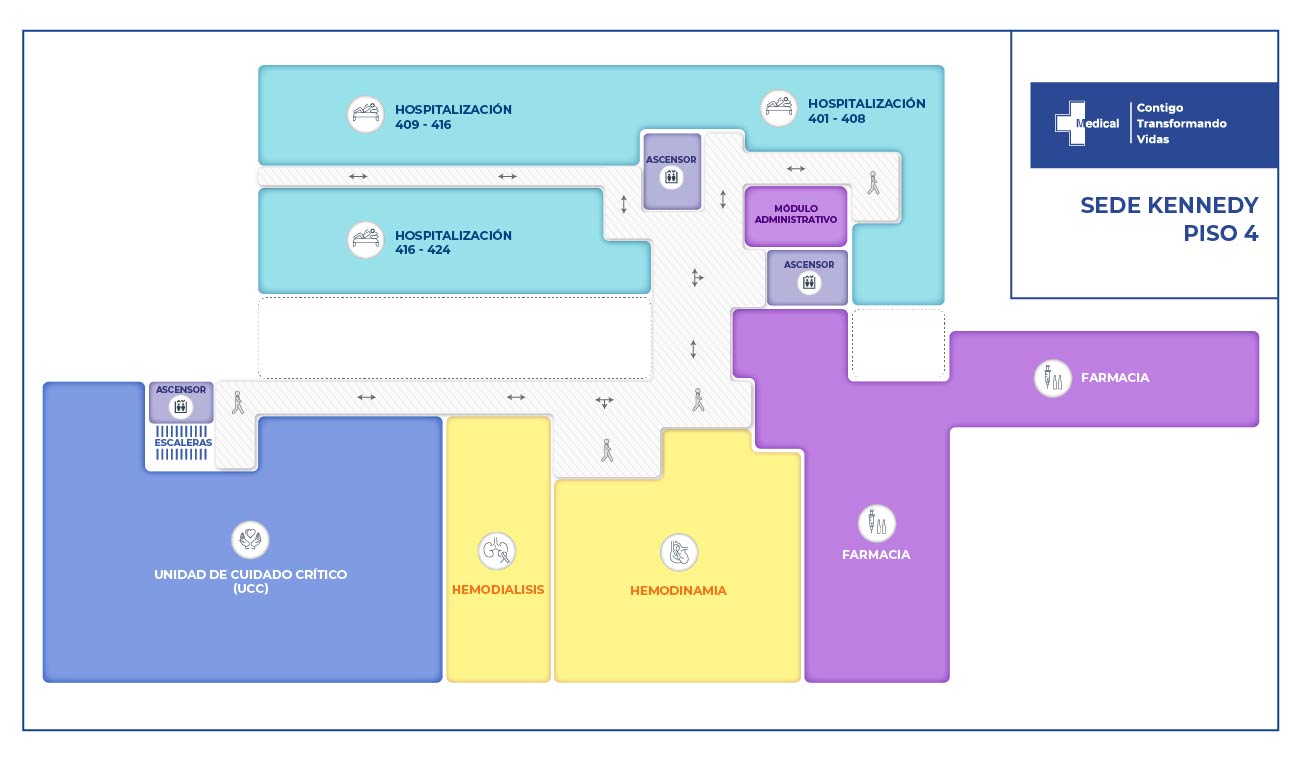

La condición de ingreso es realmente poco alentadora, sin embargo la oportunidad de los servicios, la eficiencia y eficacia que caracteriza a la clínica Medical SAS, ofrece al paciente y su familia todo un equipo interdisciplinario para la atención adecuada y secuencial para este tipo de traumas. Precedida por especialistas en cirugía general, neurocirugía, psicología, psiquiatría, servicios de apoyo terapéutico y radiológico, salas de cirugía, unidad de cuidados intensivos, rehabilitación física, clínica de heridas, entre otros.

Nuestros resultados se obtienen gracias a la integralidad, oportunidad en los servicios, contamos con profesionales altamente especializados en este tipo de traumas, brindando al paciente y a su familia confianza y seguridad en los tratamientos instaurados.